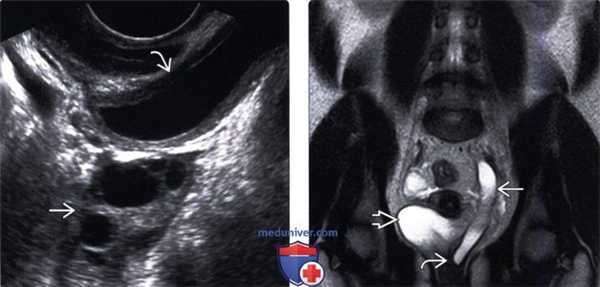

(Левый) На продольном УЗ срезе визуализируются диспластические кистозные изменения в верхнем полюсе почки, в результате обструкции, сопровождающейся потерей кортикомедуллярной дифференциации и истончением коркового вещества.

(Правый) На продольном УЗ срезе визуализируется значительное расширение лоханки нижнего отдела почки вследствие обструкции лоханочно-мочеточникового сегмента.

(Левый) На поперечном УЗ срезе визуализируется округлое тонкостенное анэхогенное образование в полости мочевого пузыря в сочетании с уретероцеле.

(Правый) На экстреторной цистоуретрограмме визуализируется симптом завянувшей лилии с контрастированием мочеточника и лоханки нижнего отдела почки и изменением нормальной оси вследствие обструкции верхней лоханки.